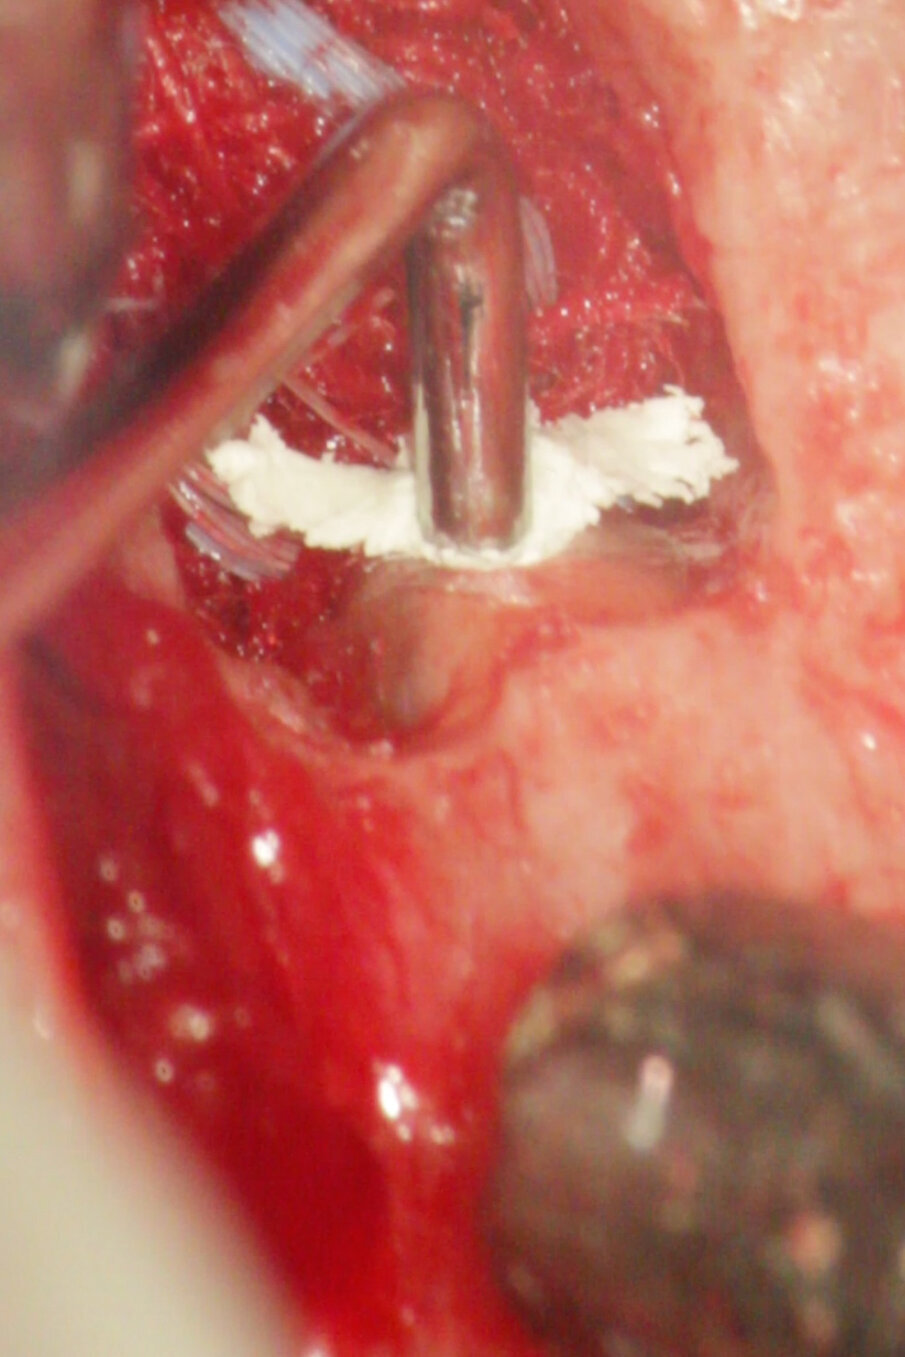

MTA è il materiale che vanta i migliori risultati come materiale da otturazione per la chirurgia apicale. L’MTA è stato associato ad una minore infiammazione, a formazione di nuovo cemento e alla rigenerazione del tessuto periradicolare (Torabinejad e Chivian 1999) (Figg. 4a-4f).